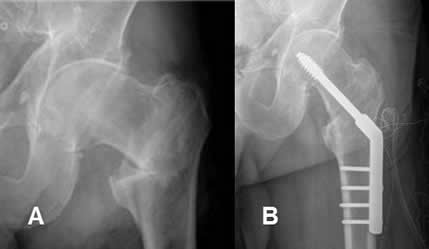

Fig 98. Tornillos de esponjosa.

A: Rx AP. Fractura espiroidea del fémur distal. Se encuentra tornillo de esponjosa en la tibia proximal (Solo roscado en la mitad distal), que fija fractura antigua.

B: Fractura bimaleolar, fijada con tornillos de esponjosa.